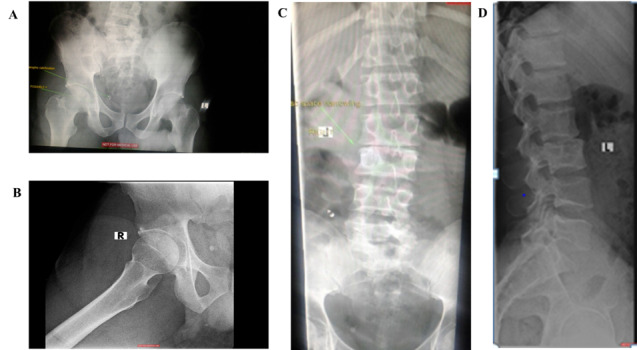

在这个临床案例中,一名男子的优势侧腹股沟受伤,他显然是在前一天的足球训练中受伤的。这名男子无法在无人帮助的情况下行走,只能用轮椅运送。咨询医生在发现很少的临床证据,X光片上也没有任何明显的迹象表明严重急性损伤后,开始怀疑。随后的详细检查显示,肌肉骨骼(MSK)和泌尿生殖道(GUT)系统的肺外结核(EPTB),并伴有病理性髋臼骨折,是腹股沟损伤的原因。EPTB的治疗解决了这种情况,尽管免疫功能低下,但在五年后没有复发,也没有长期后遗症。我们介绍了临床病例和五年的随访。该病例提醒人们,其他情况可能会模仿运动损伤,并进一步说明了这种情况的罕见表现。

In this clinical case, a man presented with a groin injury on his dominant side, which he apparently sustained in football (soccer) practice on the previous day. The man was unable to walk unassisted and had to be transported in a wheelchair. The consulting practitioner grew suspicious upon finding minimal clinical evidence and nothing notable on the X-ray to suggest a severe acute injury. A subsequent detailed workup revealed extrapulmonary tuberculosis (EPTB) of the musculoskeletal (MSK) and genitourinary tract (GUT) systems, complicated by a pathological fracture of the acetabulum, as the cause of the groin injury. Management of the EPTB resolved the condition with no relapse nor long-term sequelae beyond five years, despite being immunocompromised. We present the clinical case and a five year follow-up. The case serves as a reminder of the possibility that other conditions may mimic sports injuries and further illustrates a rare presentation of such a condition.